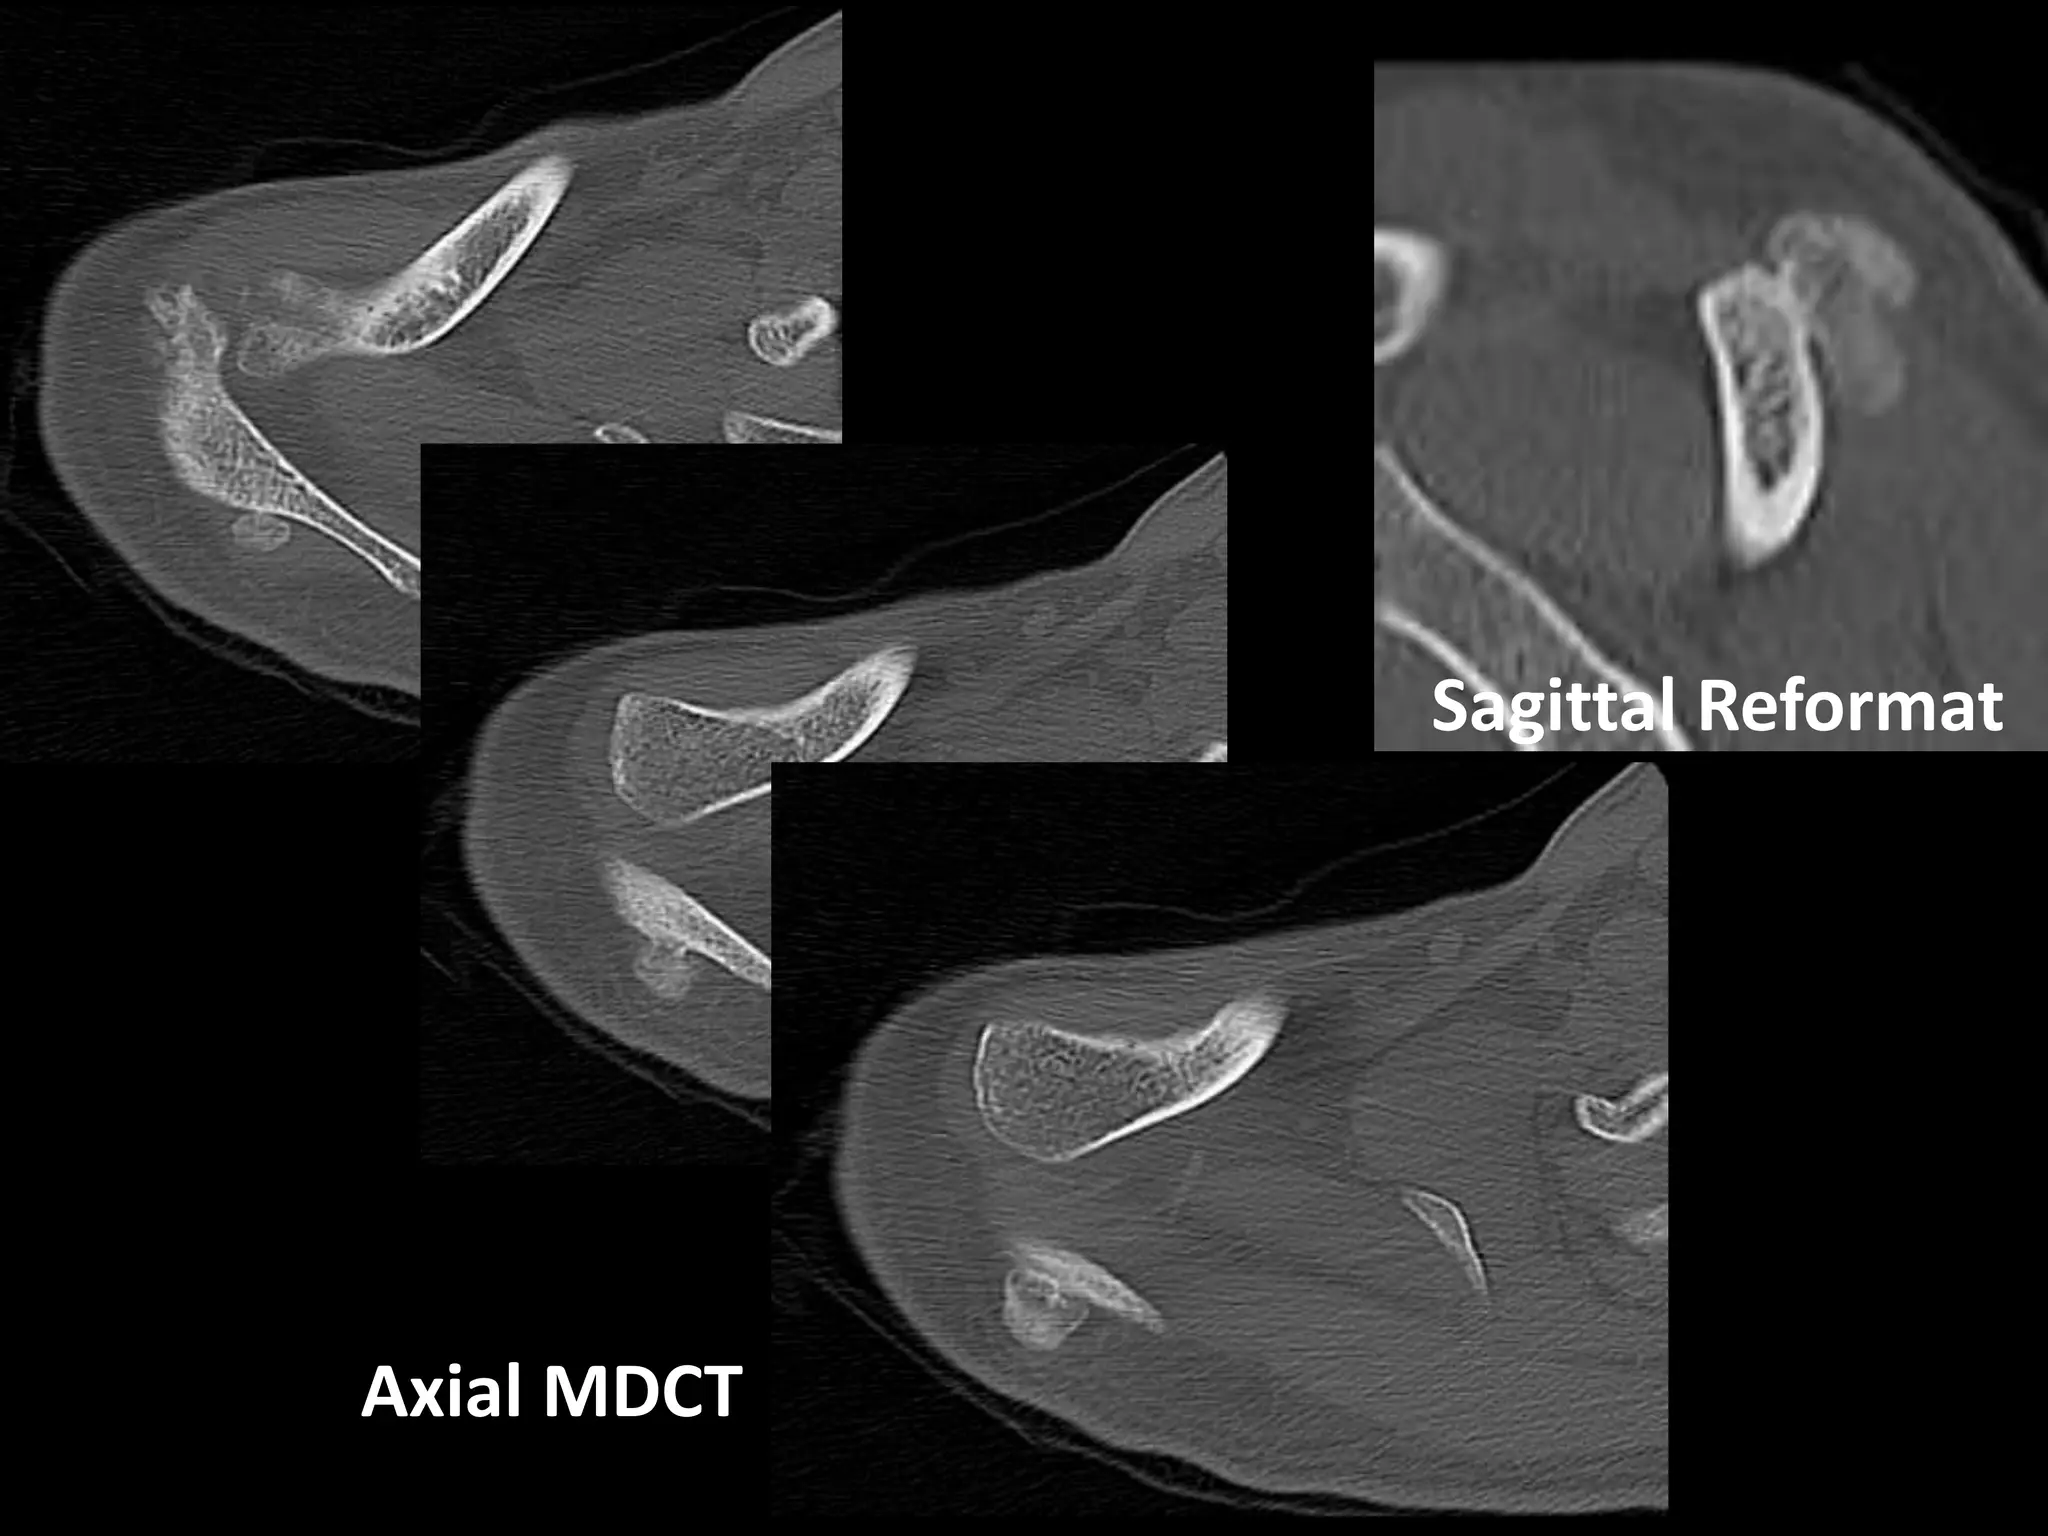

Case 3

History

• 32 y.o. man, otherwise healthy, office worker

• Noted firm, somewhat tender mass along

posterior right (dominant) shoulder 1 month prior

• Did not cause shoulder pain or affect range of

motion

• No other masses

• Physical Exam – firm, well-circumscribed non-

mobile mass that was rigidly attached to the

scapula

Sagittal Reformat

Axial MDCT